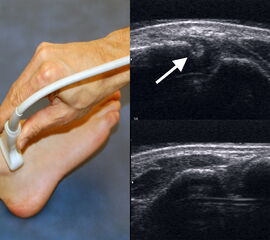

Ultraschall

Studien konnten zeigen, dass die dynamische Ultraschalluntersuchung eine sehr hohe Sensitivität und Spezifität zur Beurteilung von Syndesmosenverletzungen hat 37. Auf Höhe der Syndesmose wird dabei die coronare Translation der Fibula gegenüber der Tibia im Vergleich zur Gegenseite beurteilt. Obwohl die dynamische Ultraschalluntersuchung ein sehr präzises und kostengünstiges Diagnostikmittel ist, setzt sie ein hohes Maß an Übung voraus. Darüberhinaus können Begleitverletzungen wie zum Beispiel Osteochondrale Läsionen oder Knochenmarködeme nicht detektiert werden 38.

Quelle Abbildung 4: Sonographische Diagnostik an Sprunggelenk und Fuß , H. Gaulrapp